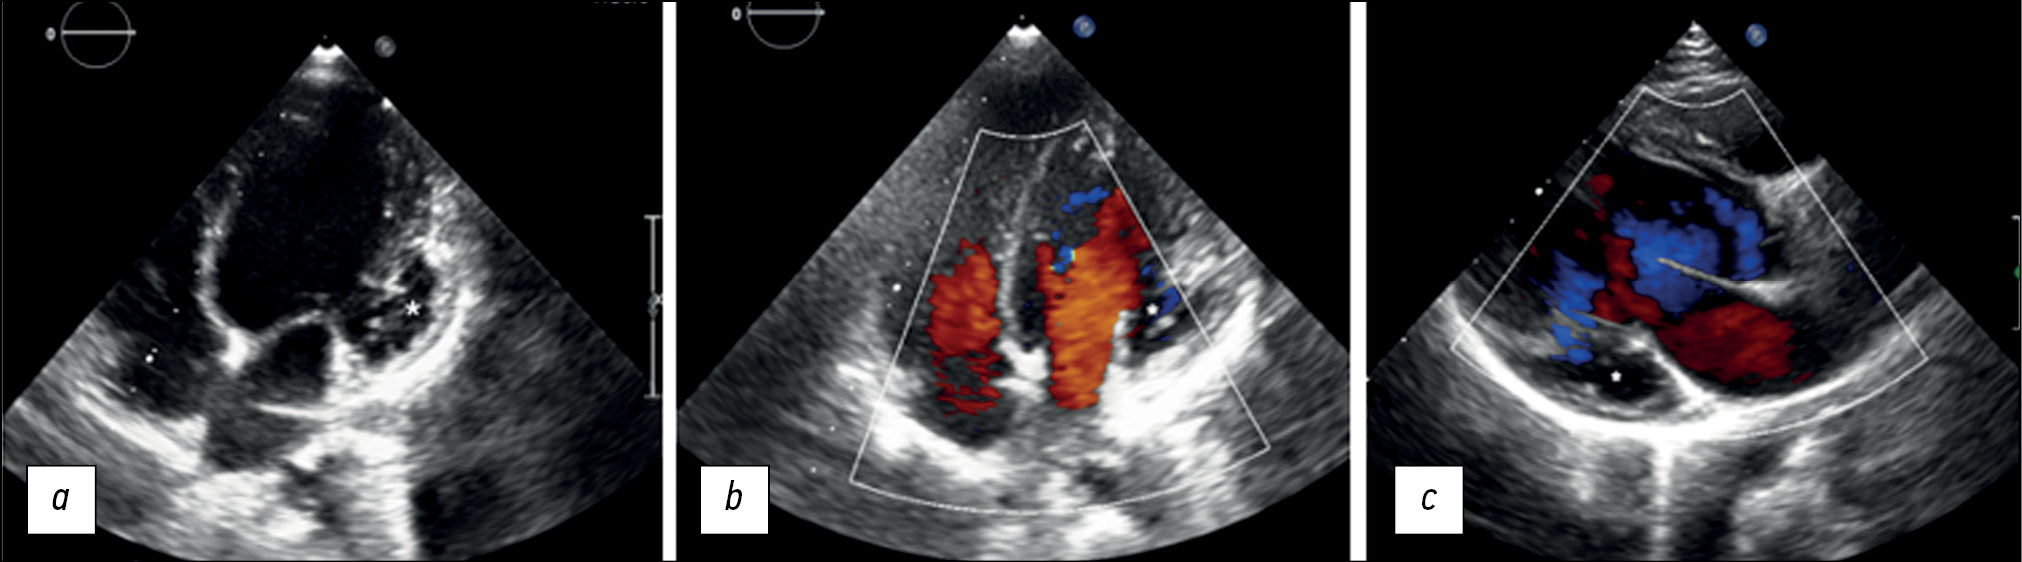

左室心肌致密化不全是一种罕见的心肌病。它通常伴有心室动脉瘤。本文描述了一个6岁女孩的临床病例。这名女孩因主诉在体育活动时身体不适而被送进本诊所。超声心动图检查显示了左心室壁有明显的小梁,侧壁基底部有隆起。这些症状与左心室动脉瘤和左室心肌致密化不全相符。心脏磁共振成像显示了,非致密层与致密层的比例为2.6:1,证实了存在左室心肌致密化不全。此外,还发现了收缩功能障碍和伴有心肌瘢痕形成的左心室动脉瘤。冠状动脉造影排除了冠状动脉病变。在这种情况下,我们可以认为心内膜瘢痕形成的性质是非致密心肌层微循环障碍的结果。